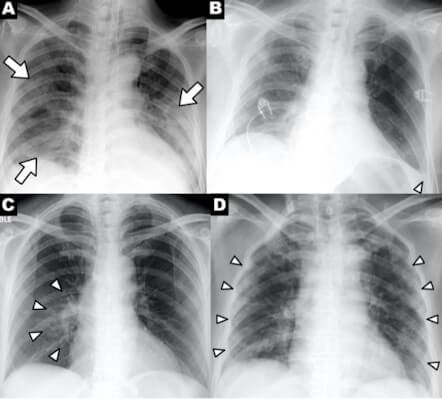

На фото: Серия рентгеновских снимков грудной клетки пациентов с COVID-19, показывающих клинические признаки болезни: А) неоднородные уплотнения, В) плевральный экссудат, С) перихилярная локализация и D) периферическая локализация. Снимки предоставлены RSNA.

Какие особенности на рентгеновском снимке указывают на COVID-19? Рентгенография грудной клетки может показывать неравномерные или диффузные асимметричные помутнения лёгочной ткани, похожие на пневмонию, но вызванную другими коронавирусами, говорится в статье доктора Джонатана Родригеса и его коллег, опубликованной 23 марта в журнале Clinical Radiology.